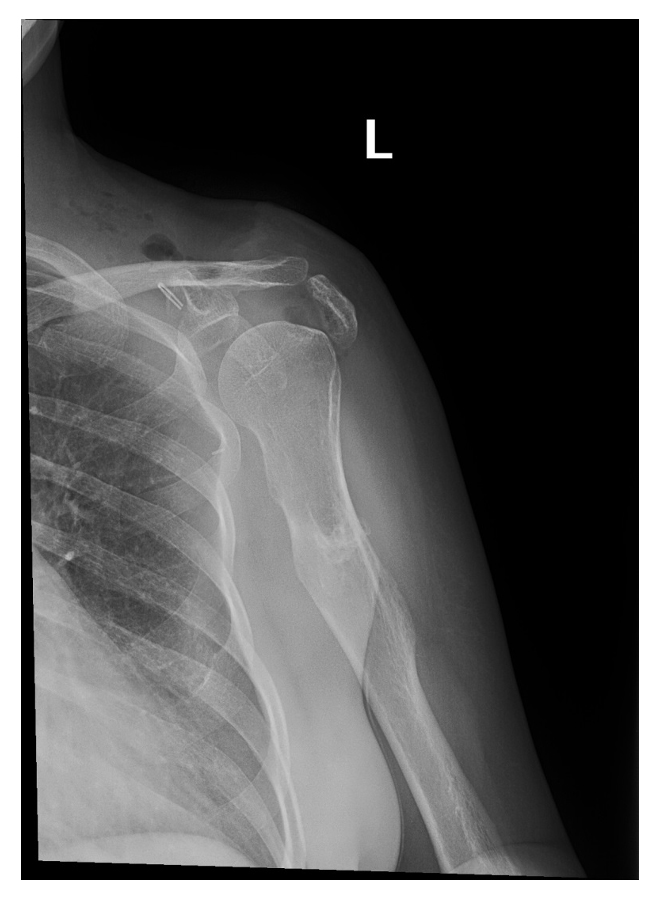

Ameliyat Öncesi: Röntgende skapula kaynaklı dev boyutlu düzensiz sınırlı kıkırdak doku içeren kitle görünmekte.

Ameliyat Sonrası: Röntgende glenoid eklem yüzü hariç totale yakın skapulektomi uygulandığı görünmekte.